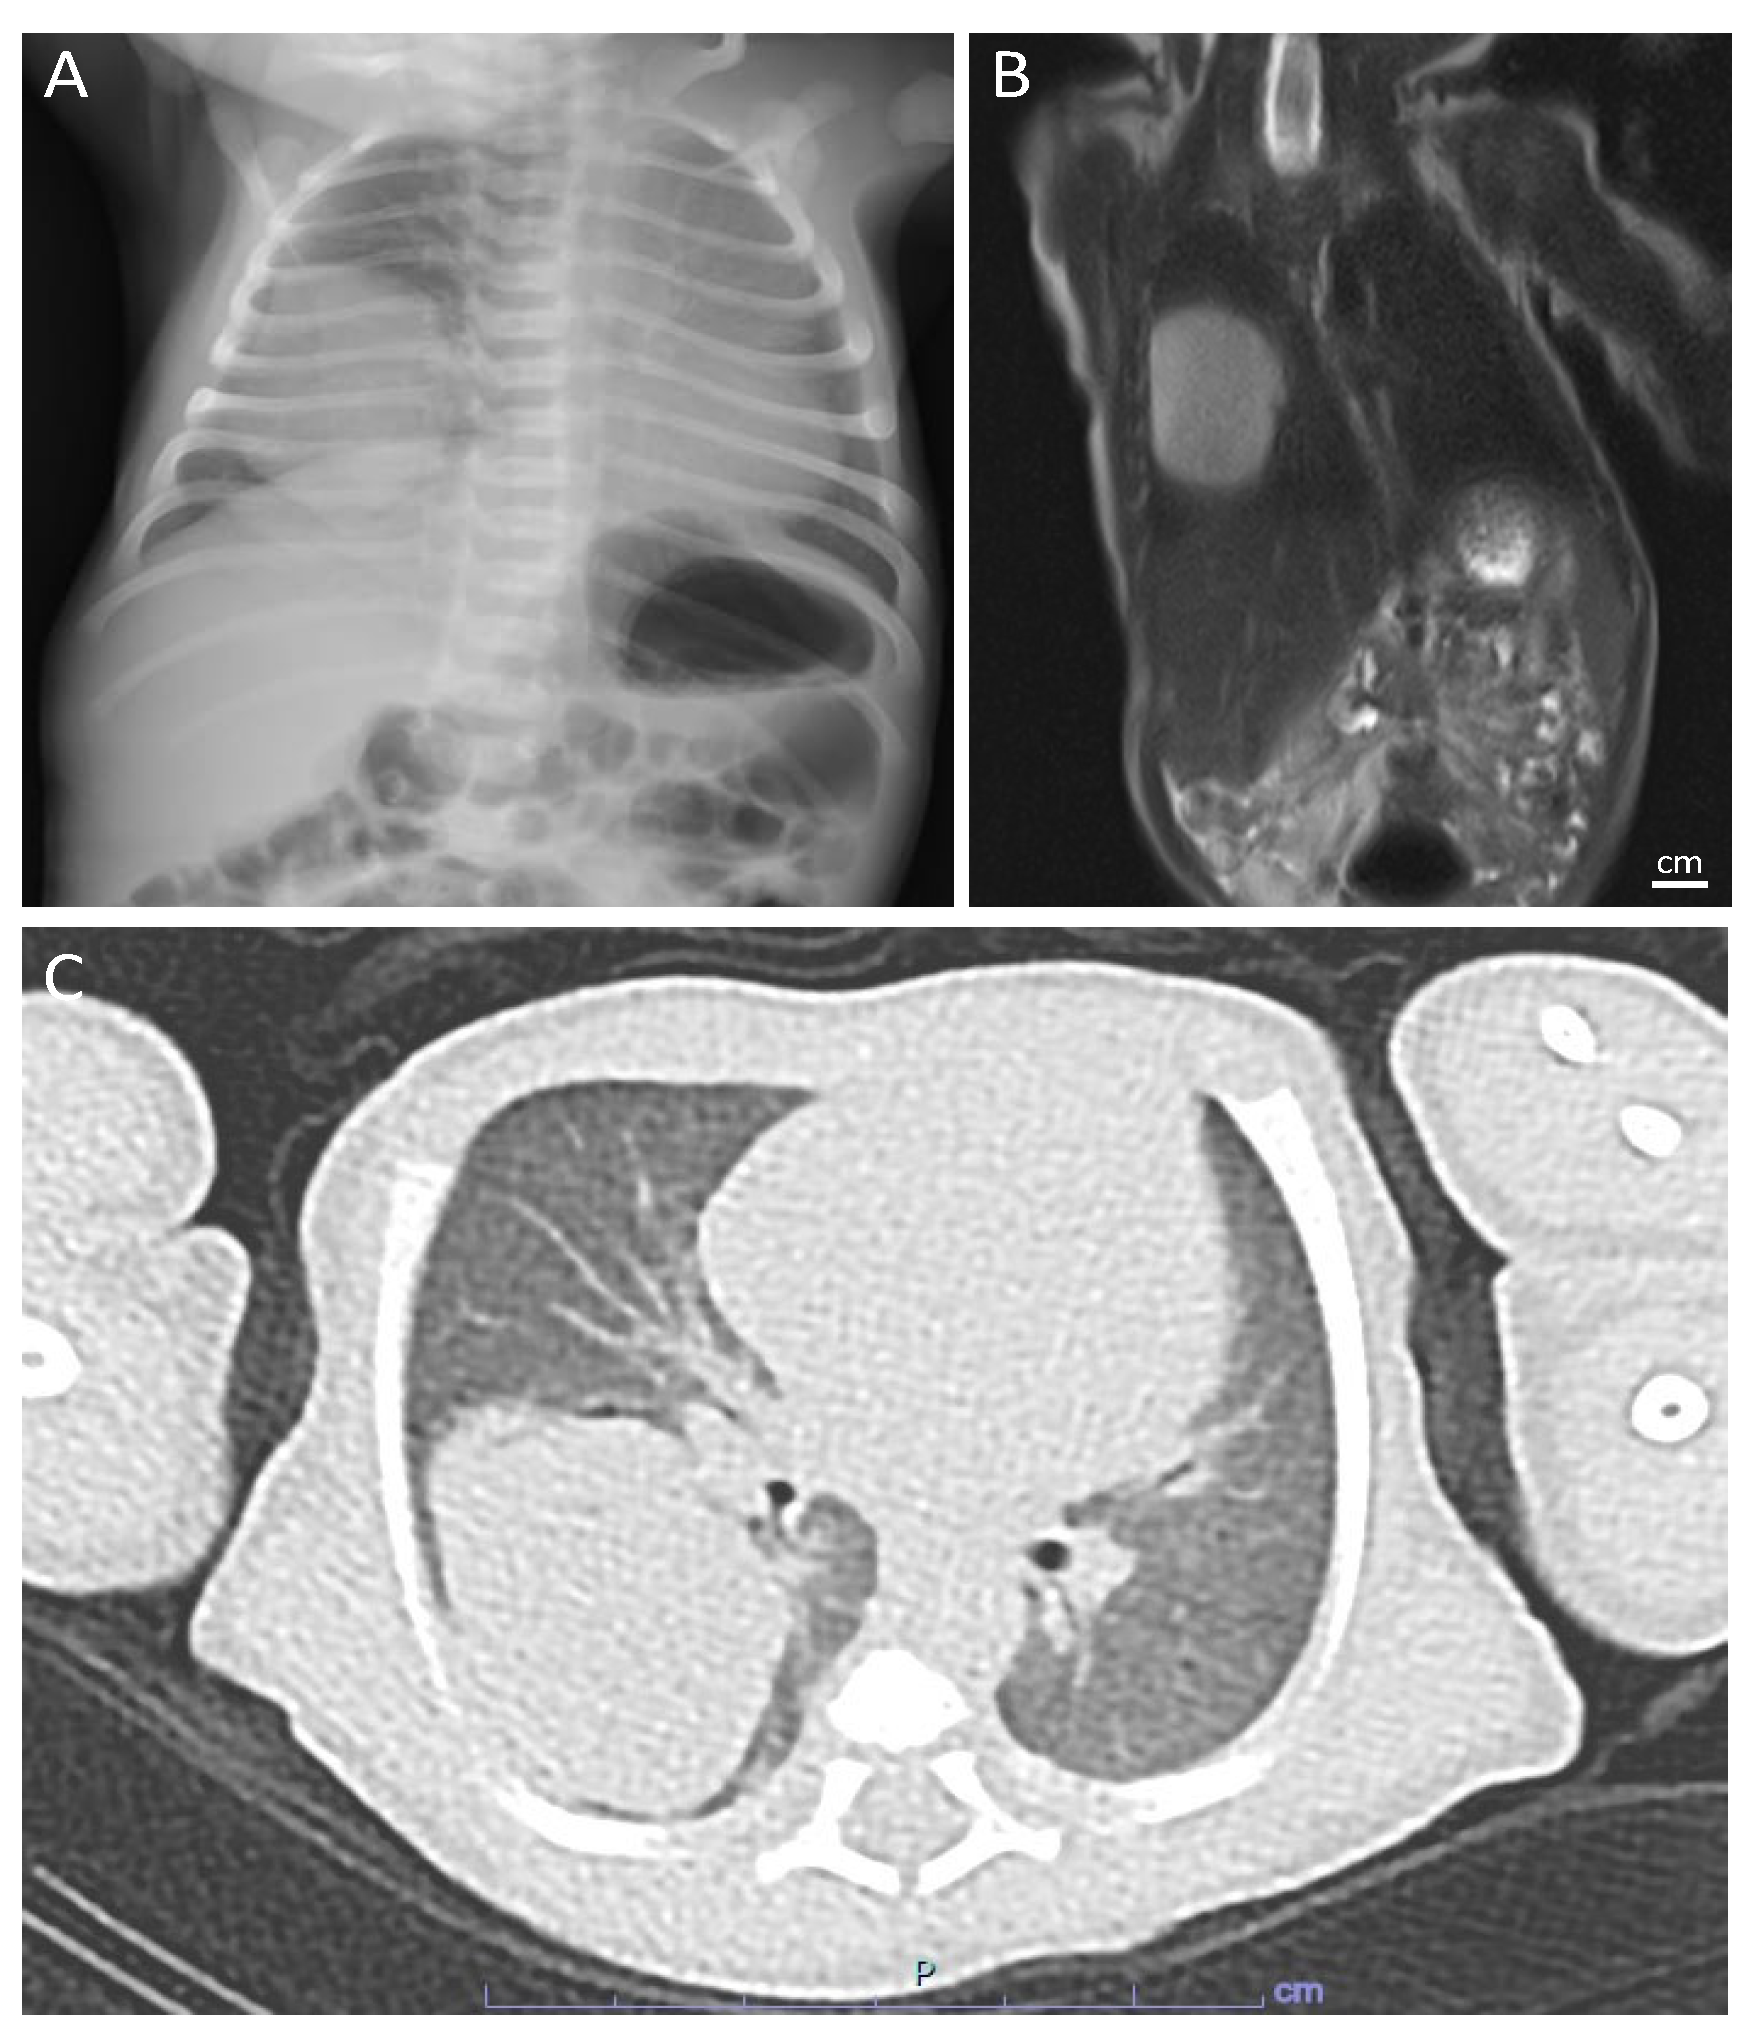

| Present case | 22 | M | Birth | Respiratory distress | 18 days | Right lower lobe | Lobectomy | 3.5 | Solid | No recurrence, 14 months |